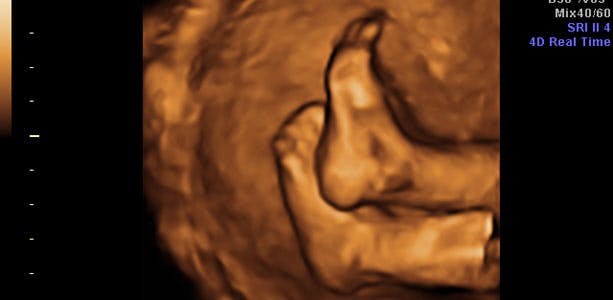

Gravid uge 29: Sul på kroppen

Fra 7. måned i en graviditet er barnets vækst afhængig af hormonet insulin, som stimulerer til optagelse af sukker fra blodet. Inde i cellerne bruges sukkeret til at danne proteiner og fedt, og dermed give dit barn "sul" på kroppen. I de sidste uger af din graviditet tager barnet i gennemsnit 200 gram på om ugen. De, børn der vægtmæssigt ligger over gennemsnittet, kan tage op til 300 gram på om ugen. I slutningen af ugen vejer barnet cirka 1400 gram.